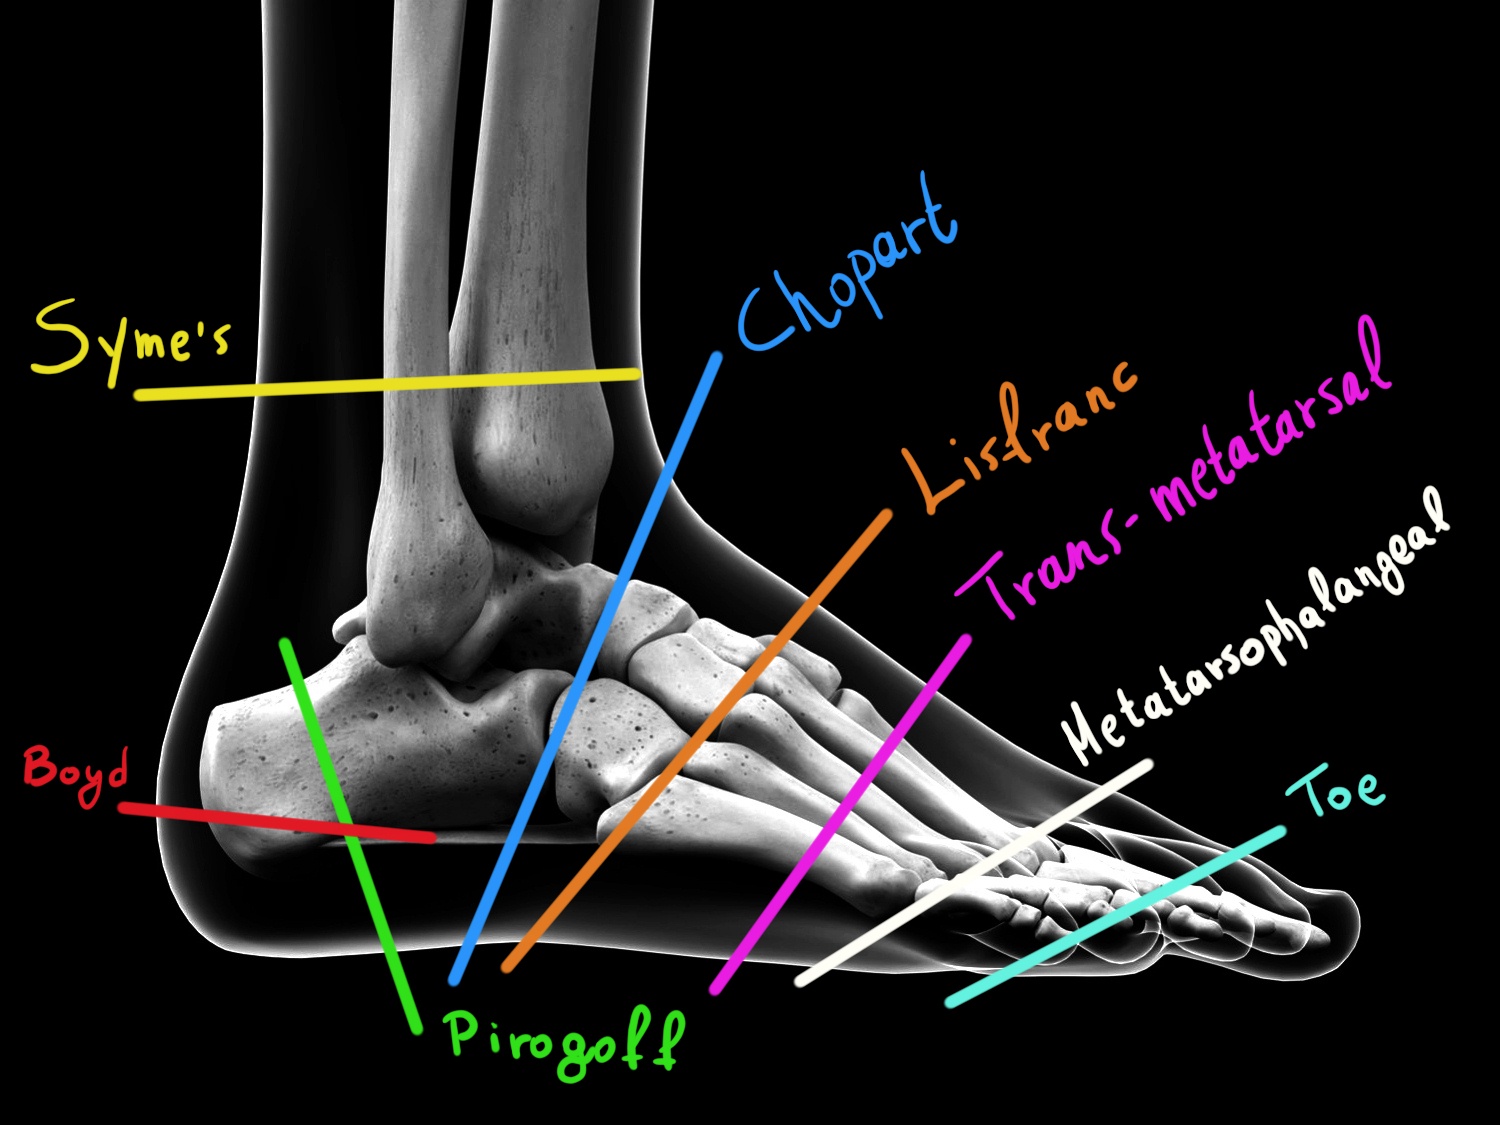

Είδη ακρωτηριασμών άκρου ποδός